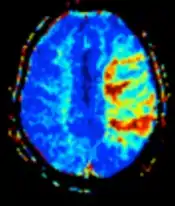

| صورة الانتشار | المعتاد | DWI | قياس الحركة البراونية لجزيئات الماء.[13] | إشارة عالية خلال دقائق من احتشاء الدماغ.[14] | ![]() |

| معامل الانتشار الظاهري | ADC | تقليل الوقت الأفقي من خلال التقاط صور انتشار معتاد بأوزان مختلفة، وأيضا من خلال التغير المقابل للانتشار.[15] | إشارة منخفضة خلال دقائق من احتشاء الدماغ.[16] | ![]() | |

| صورة التروية | صبعة ديناميكية قابلة للتمغنط | DSC | بحقن صبغة الجادولينيوم لتقوم الصور المتكررة والسريعة بتقييم فقد الإشارة المستحث بقابلية التمغنط.[19] | في احتشاء الدماغ يتُظهر منطقة وسط الاحتشاء والظل الناقص نقص بالتروية.[20] | ![]() |

الانتشار

كما يُعد التصوير بالرنين المعناطيسي الموزون بالانتشار أحد تطبيقات صورة الانتشار في الرنين المغناطيسي، والذي يكون شديد الحساسية للتغيرات الحادثة بعد السكتة الدماغية،[42] حيث يُنظر إلى الزيادة في حجم التقييد (الحواجز) أمام انتشار الماء ( نتيجة للوذمة الخلوية السامة) على أنها المسؤولة عن ارتفاع الإشارة أثناء التصوير، ويظهر ذلك في غضون من 5-10 دقائق من وقت ظهور أعراض السكتة الدماغية ويبقى لمدة تصل إلى أسبوعين (مقارنة بالتصوير المقطعي المحوسب والذي لا يكتشف تغيرات الاحتشاء الحاد غالبا إلا بعد مدة تصل إلى 4-6 ساعات،. وبالاقتران مع تصوير التروية الدماغية فإنه يُمكن للباحثين تسليط الضوء على مناطق "عدم تطابق التروية / الانتشار" التي قد تشير إلى المناطق التي يُمكن إنقاذها عن طريق العلاج بإعادة التروية (استئصال أو انحلال الخثار).

التروية

يتم إجراء التصوير الموزون بالتروية من خلال 3 تقنيات رئيسية:

- الصبعة الديناميكية القابلة للتمغنط: حيث يتم حقن صبغة الجادولينيوم، ويحدد التصوير المتكرر والسريع فقدان الإشارة الناجم عن قابلية التمغنط.[43]

تُعالج بعد ذلك البيانات الناتجة للحصول على خرائط التروية بقياسات مختلفة ، مثل حجم الدم وتدفق الدم ومتوسط وقت العبور ووقت الوصول للذروة.

تنخفض التروية في منطقة الظل الناقص أثناء احتشاء الدماغ،[20] ويقوم تتابع التصوير بالرنين المغناطيسي الموزون بالانتشاربتقدير كمية الأنسجة الميتة بالفعل، وبالتالي يمكن استخدام مزيج من هذه التتابعات لتقدير كمية أنسجة المخ التي يمكن إنقاذها عن طريق استئصال أو انحلال الخثار.